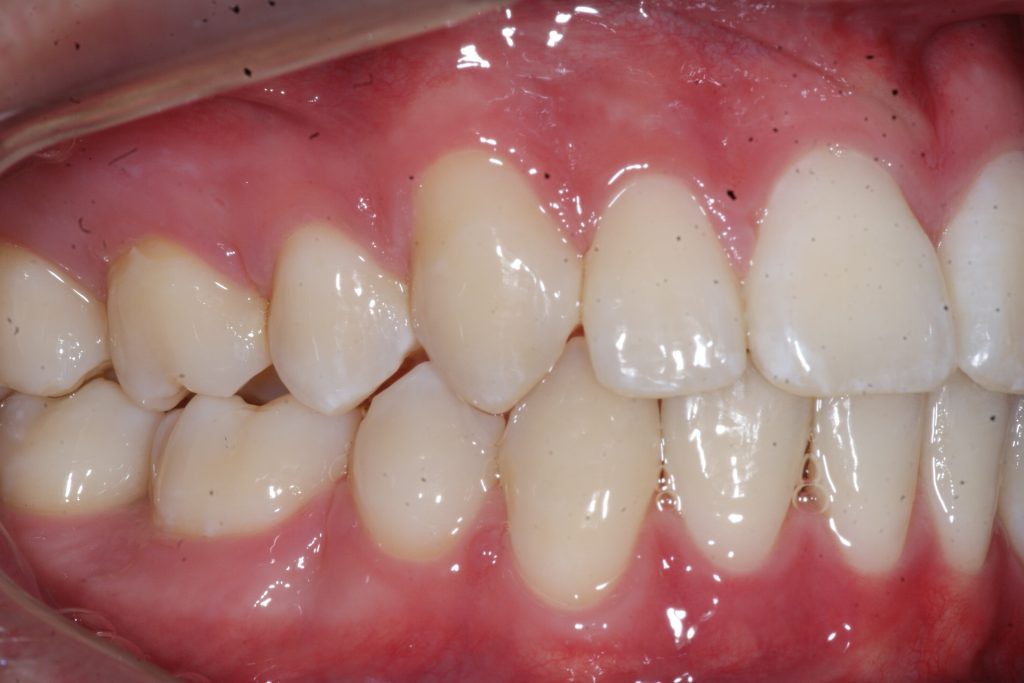

Correction d’une malocclusion de type bimax, canine #33 ectopique et chevauchement léger aux 2 arcades.  Des appareils fixes (broches) et extraction de 4 prémolaires furent nécessaires pour améliorer ce sourire.  Traitement chez un jeune adulte, réalisé en 28 mois.